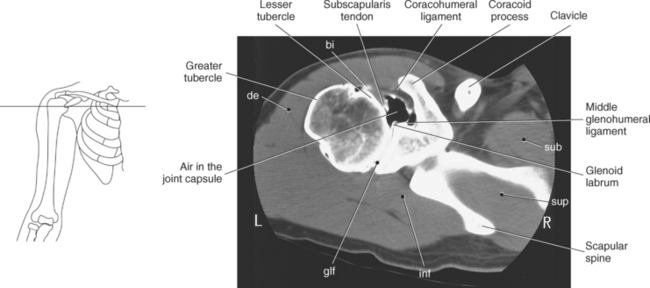

The scapula is a triangular-shaped flat bone that forms the posterior portion of the shoulder girdle. It has a medial margin, a lateral margin, and a superior margin. The margins are separated by the superior, inferior, and lateral angles (Figures 9.2 and 9.3). The anterior surface of the scapula, subscapular fossa, is flat and slightly concave. The posterior surface of the scapula is divided by the scapular spine into a smaller supraspinous fossa, and a larger infraspinous fossa (Figure 9.7). Four projections of the scapula provide attachment sites for the muscles and ligaments contributing to the shoulder girdle. These include the scapular spine, acromion, coracoid process, and glenoid process (Figures 9.7 through 9.10). The scapular spine arises from the upper third of the posterior surface of the scapula and extends obliquely and laterally to give rise to a flattened process termed the acromion. Located on the anterolateral surface of the scapula is a beaklike process termed the coracoid process, which arises just medial to the glenoid process and functions to protect the shoulder joint, which lies beneath it. The coracoid process is an attachment site for the pectoralis minor, short head of the biceps brachii, and the coracobrachialis muscles. The scapular notch is located just medial to the coracoid process, on the superior margin of the scapula and allows for the passage of the suprascapular nerve (Figure 9.2). The glenoid process, the largest of the projections, forms the lateral angle of the scapula and ends in a depression called the glenoid fossa (glenoid cavity) (Figures 9.7 through 9.9). There are two tubercles associated with the glenoid fossa, an upper supraglenoid tubercle and a lower infraglenoid tubercle, which serve as attachment sites for the biceps brachii and triceps brachii (Figure 9.8). The shallow articular surface of the glenoid fossa joins with the relatively large articular surface of the humeral head to create the freely moving glenohumeral joint (Figures 9.2, 9.3, 9.11, and 9.12).

The humerus is a long bone that articulates with the scapula superiorly and the radius and ulna inferiorly. It consists of a body or shaft, a lower end (distal end), and an upper (proximal) end (Figure 9.13). The proximal end is formed by the head of the humerus. Two tubercles project from the humeral head to provide attachment sites for tendons and ligaments. The lesser tubercle is located on the anterior surface of the humeral head, whereas the greater tubercle is located on the lateral surface of the humeral head (Figures 9.12 through 9.15). The tubercles are separated by the intertubercular (bicipital) groove, which is bounded by the crests of the lesser and greater tubercles as it descends the humerus (Figures 9.9 and 9.13 through 9.15). The humerus has two necks, the more proximal anatomic neck and the surgical neck, located inferior to the tubercles just distal to the humeral head (Figures 9.13 and 9.16). In the middle of the body or shaft of the humerus, on the anterior surface, is the roughened area of the deltoid tuberosity that gives attachment for the deltoid muscle (Figure 9.13).

The edge of the glenoid fossa is surrounded by a fibrocartilaginous ring termed the glenoid labrum (glenoid lip) (Figure 9.17). The glenoid labrum is a fold of the articular capsule, which functions to deepen the articular surface of the glenoid fossa. Superiorly, the labrum blends with the long head of the biceps brachii muscle. In cross section it appears triangular (Figure 9.18). The three glenohumeral ligaments (superior middle, and inferior) are thickenings of the fibrous capsule that surrounds the shoulder joint; they contributes to the formation of the glenoid labrum (Figures 9.17 and 9.19). They extend from the supraglenoid tubercle of the scapula to the lesser tubercle of the humerus. Also aiding in strengthening the fibrous capsule is the coracohumeral ligament that passes from the lateral side of the coracoid process of the scapula to the anatomic neck of the humerus (Figure 9.19). The coracoacromial ligament is another important ligament located on the anterior portion of the shoulder. As this ligament joins the coracoid process and acromion, it forms a strong bridge, termed the coracoacromial arch, which protects the humeral head and rotator cuff tendons from direct trauma and prevents displacement of the humeral head superiorly (Figures 9.17 and 9.19). The coracoclavicular ligaments help to maintain the position of the clavicle, in relation to the acromion, by spanning the distance between the clavicle and coracoid process of the scapula (Figure 9.19). The acromioclavicular ligament, at the acromioclavicular joint, provides support for the superior surface of the shoulder (Figures 9.17 and 9.19). The transverse humeral ligament is a broad band of connective tissue passing from the greater tubercle to the lesser tubercle of the humerus, forming a bridge over the intertubercular groove for protection of the long head of the biceps tendon (Figure 9.19). The ligaments of the shoulder are demonstrated in Figures 9.20 through 9.30.